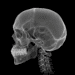

A radiografia panorâmica é um exame radiológico que capta a imagem de toda a boca em uma única radiografia, permitindo uma visualização ampla da maxila, mandíbula e os dentes. Diferente das radiografias intraorais, que mostram cada dente individualmente, a panorâmica usa a técnica de tomografia rotacional. Isso significa que o feixe de radiação gira ao redor da cabeça do paciente, criando uma imagem bidimensional das estruturas dentárias.

Com o paciente devidamente posicionado, o aparelho começa a girar em torno da cabeça, emitindo radiação. O tempo de exposição é geralmente curto, variando de 10 a 30 segundos. O resultado é uma imagem que mostra toda a estrutura das arcadas dentárias e os maxilares de maneira clara.